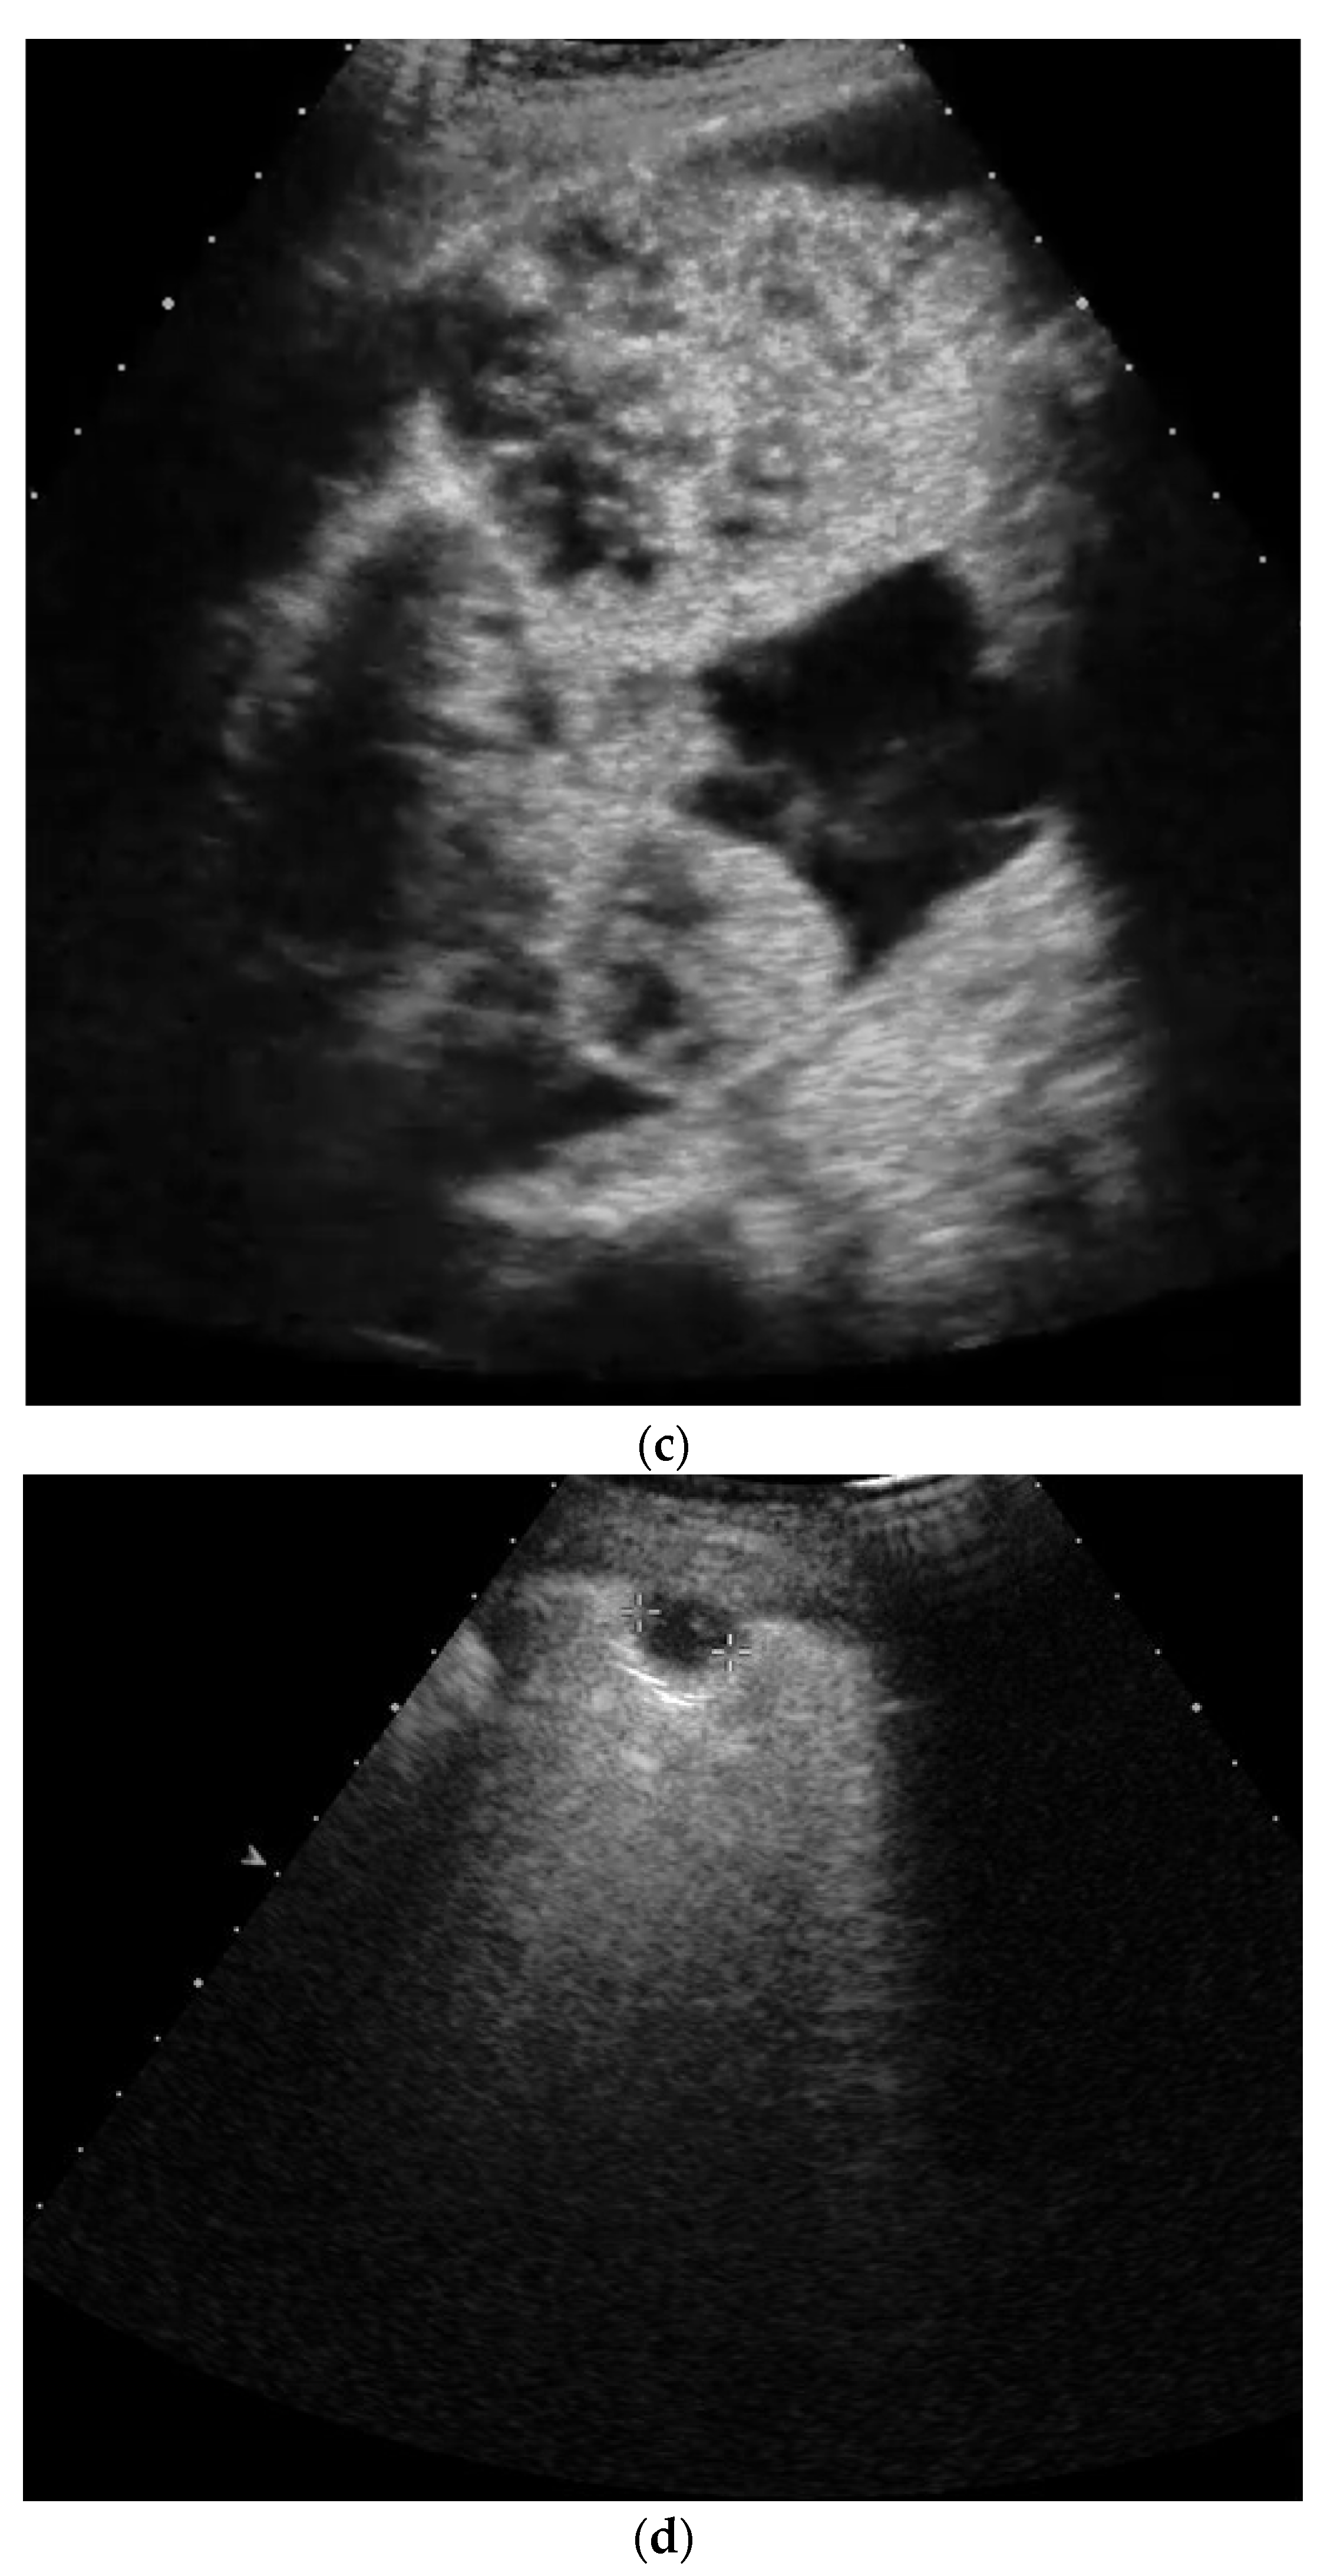

3. Pleural Mesothelioma